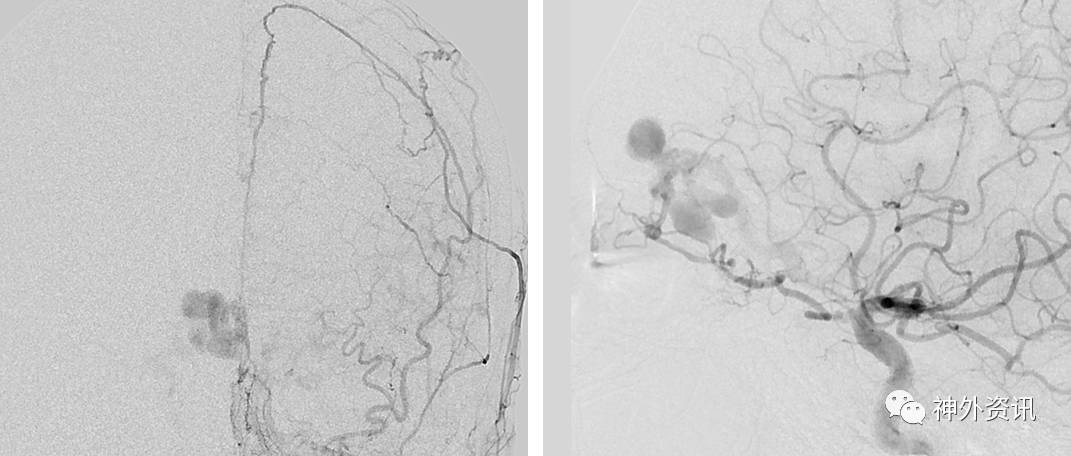

图1. 左侧颈外动脉的前后位血管造影(左图)和侧位血管造影(右图)提示筛骨dAVF,由筛前动脉和大脑镰动脉供血,引流至伴有静脉曲张的皮层静脉,可见静脉动脉化。